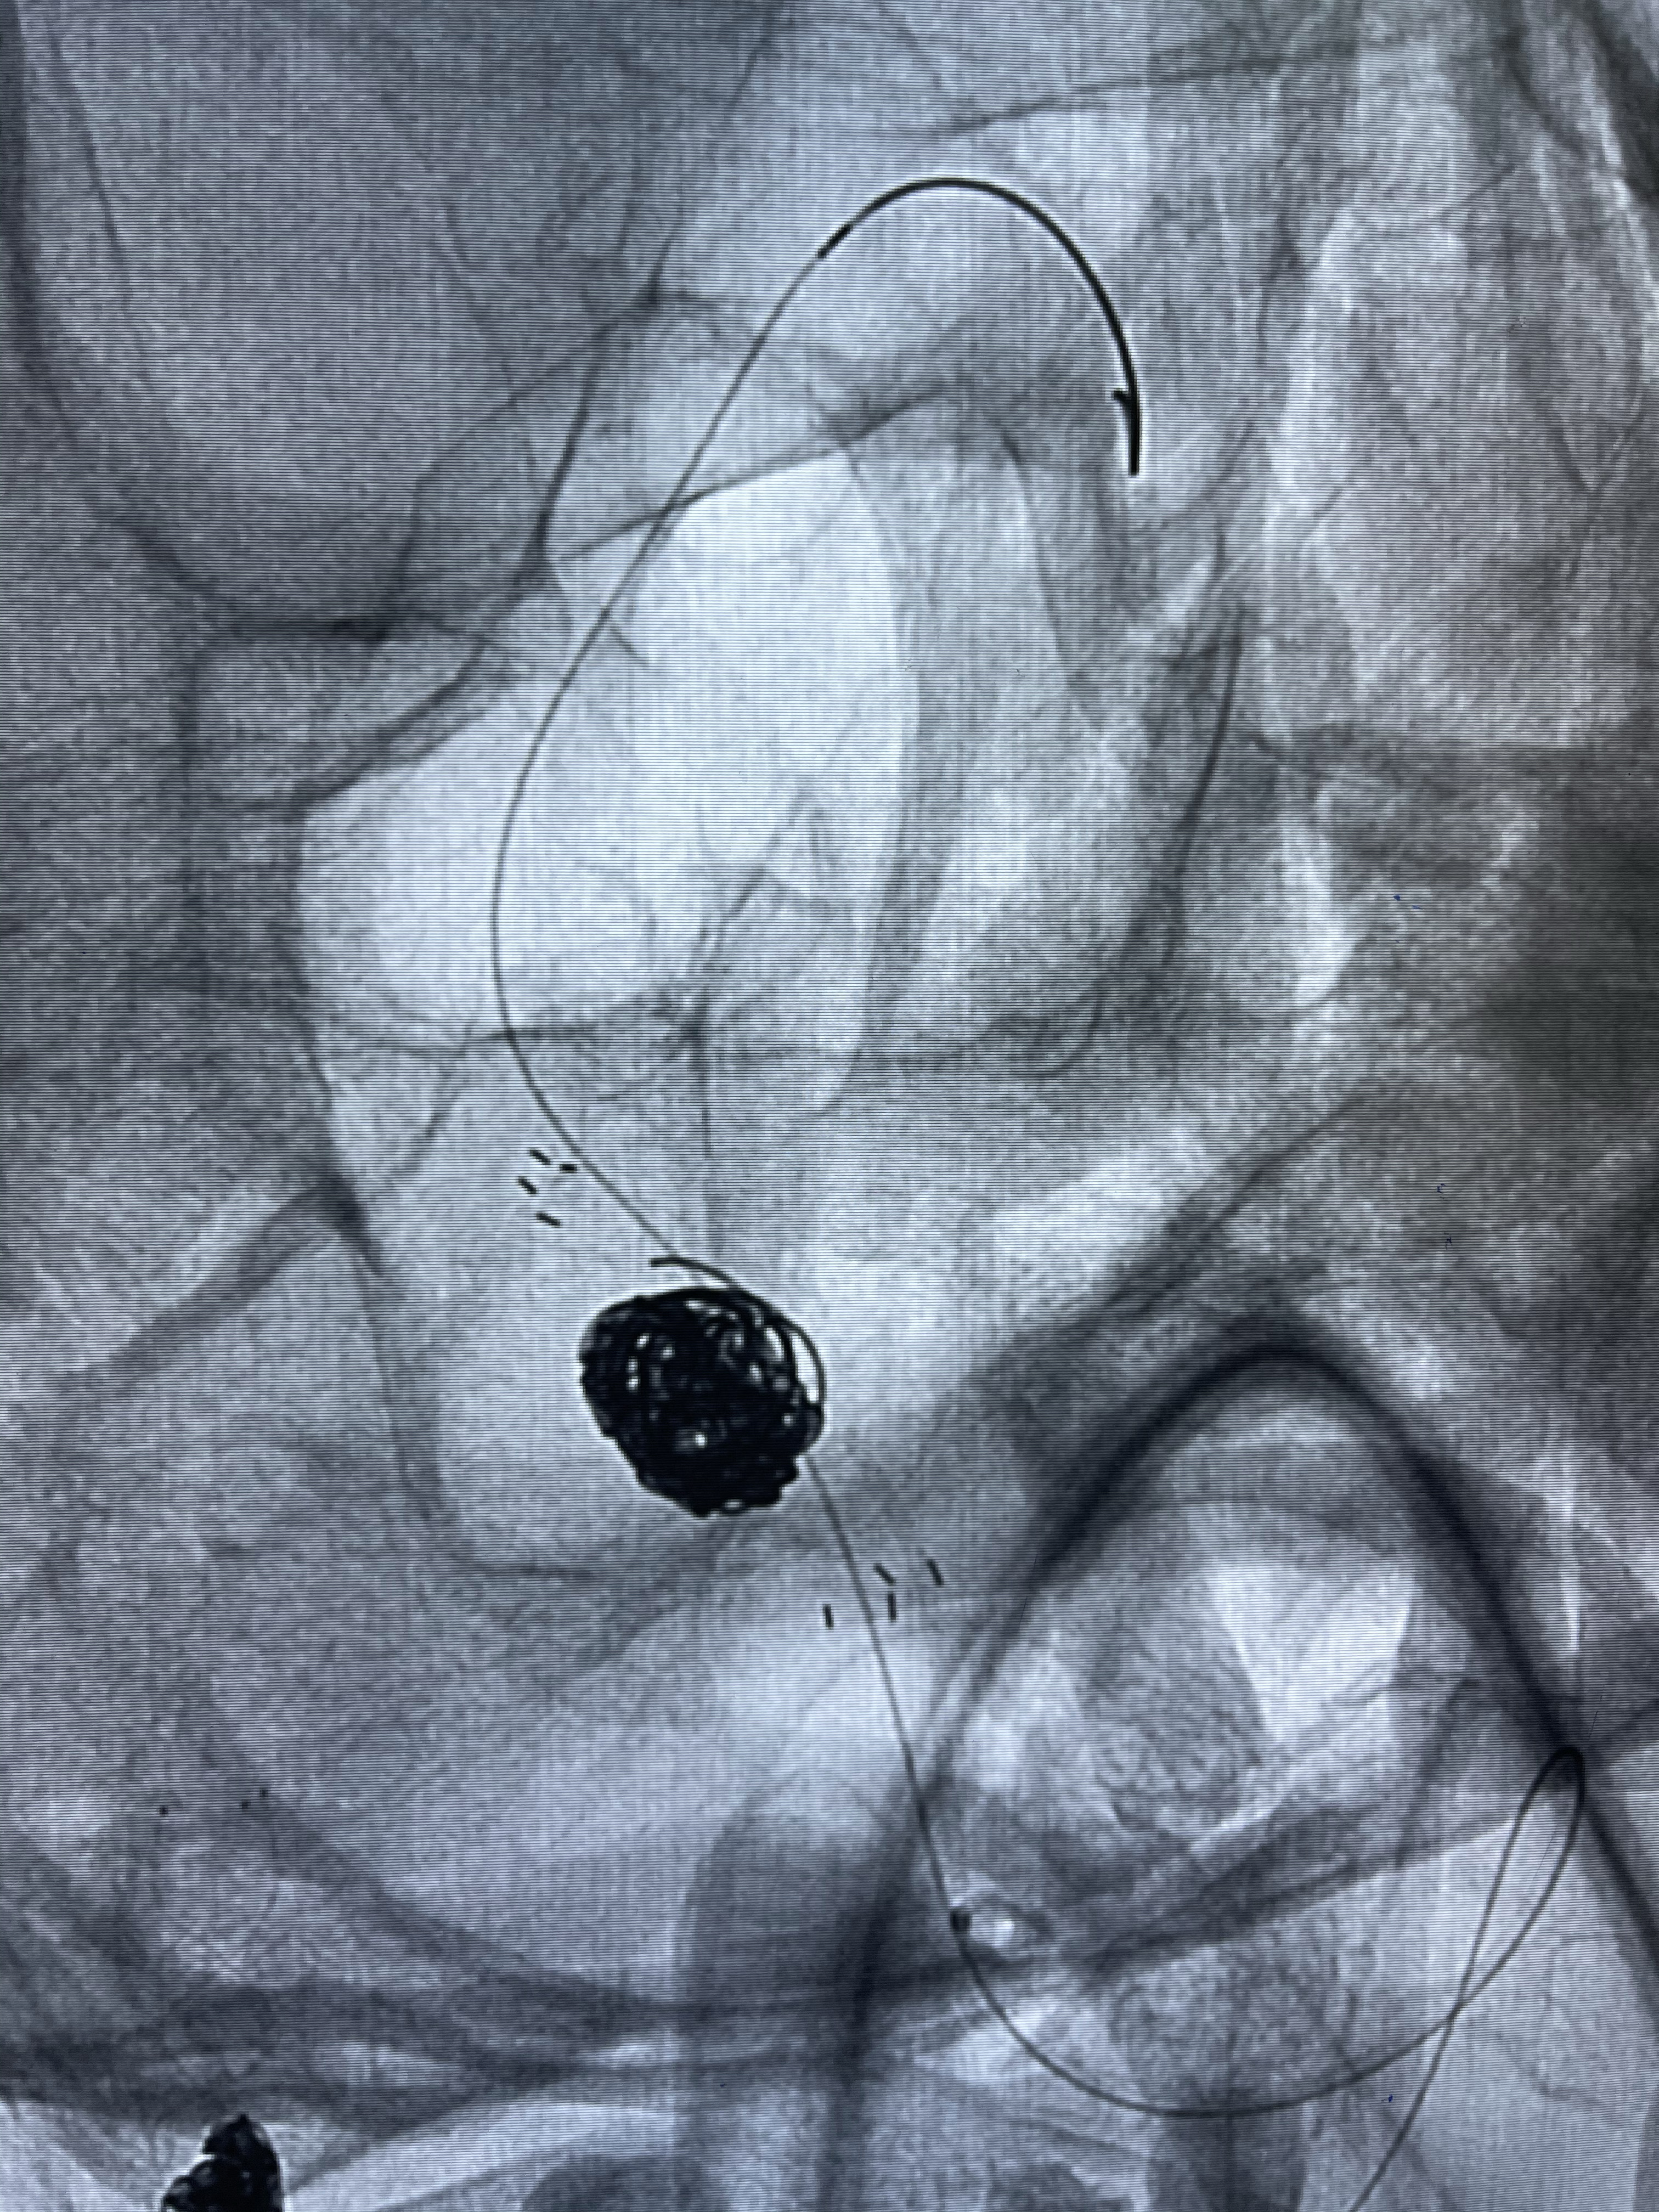

支架释放,透视下

2.Tubridge3.5-30mm密网支架

术后即刻CT